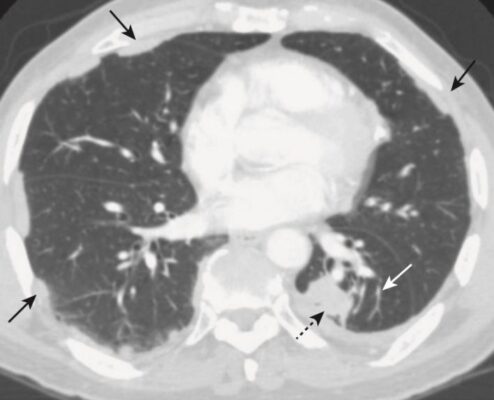

Xẹp phổi tròn (Round atelectasis)

- Hình thức xẹp phổi này thường thấy ở ngoại vi đáy phổi và do sự kết hợp của bệnh màng phổi trước đó (chẳng hạn như tiếp xúc với amiăng hoặc lao) và gây tràn dịch màng phổi tạo ra xẹp phổi cho chèn ép liền kề.

- Khi tràn dịch màng phổi rút đi, bệnh lý màng phổi nền dẫn đến một phần của phổi xẹp bị “kẹt”. Điều này tạo ra một tổn thương dạng khối có thể bị nhầm lẫn với một khối u.

- Trên chụp cắt lớp vi tính (CT) ngực, các dấu hiệu mạch máu phế quản đặc trưng dẫn từ xẹp phổi tròn quay trở lại rốn phổi, tạo ra hình dạng đuôi sao chổi (comet-tail appearance) (Hình 10).